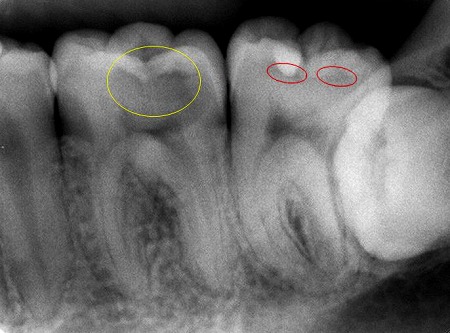

これは、3日程前に来られたある患者様のレントゲン写真です。歯がズキズキするという事で神経を殺す事になってしまいました。原因は下の写真の黄色の丸の部分の虫歯ですが、上から見てもプラスチックが詰めてあるだけで虫歯になっている様子はなかったのです。しかし麻酔してプラスチックを外すとボロボロになつていました。

赤い丸の部分はこれから虫歯が進行して行こうとしている所で、同じくプラスチックの詰め物がしてあります。

見た目は悪いですが、金属やセラミックで埋めておけば多分こんな風にはならなかったと思います。